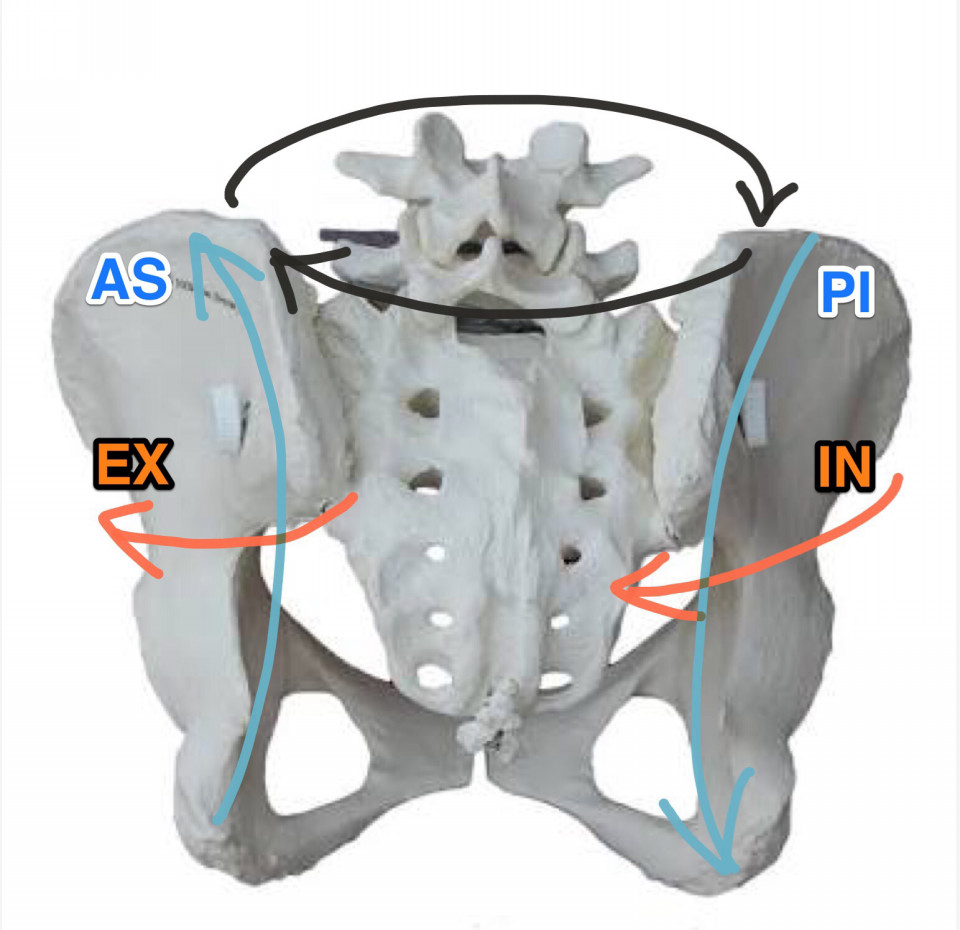

Ilium Misalignments - 骨盤の歪み方

Ilium Misalignments - 骨盤の歪み方

骨盤の触診 - PI/ASリスティングの場合

骨盤の触診 - PI/ASリスティングの場合

骨盤の触診 - EX/INリスティングの場合

骨盤の触診 - EX/INリスティングの場合

左右の骨盤の動き

左右の骨盤の動き